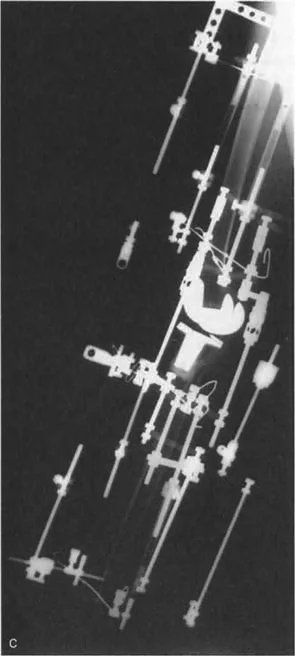

- جراحات قطع العظم وتقويم المحاور

- استبدال المفاصل في حالات التشوه الشديد

في حين أن التشوهات الديناميكية تُناقش غالبًا في سياق أمراض الأعصاب والعضلات لدى الأطفال، فإن المبادئ البيوميكانيكية التي تحكمها تنطبق عالميًا على إعادة بناء العظام لدى البالغين. يشمل ذلك سيناريوهات إعادة البناء المعقدة للغاية، مثل استبدال مفصل الركبة الكلي (TKR) واستبدال مفصل الورك الكلي (THR) المرتبطة بالانحرافات الشديدة خارج المفصل. إن فهم الأذرع الرافعة هو المتطلب الأساسي لإتقان هذه التقنيات المتقدمة في جراحة المفاصل وقطع العظم، وهو ما يتقنه الأستاذ الدكتور محمد هطيف في ممارسته اليومية.

- التصوير المقطعي المحوسب (CT Scans): يوفر صورًا ثلاثية الأبعاد للعظام، وهو مفيد بشكل خاص لتقييم التشوهات الالتوائية (مثل الورم الفخذي المفرط) وتحديد موقع مركز دوران الانحراف (CORA) بدقة.